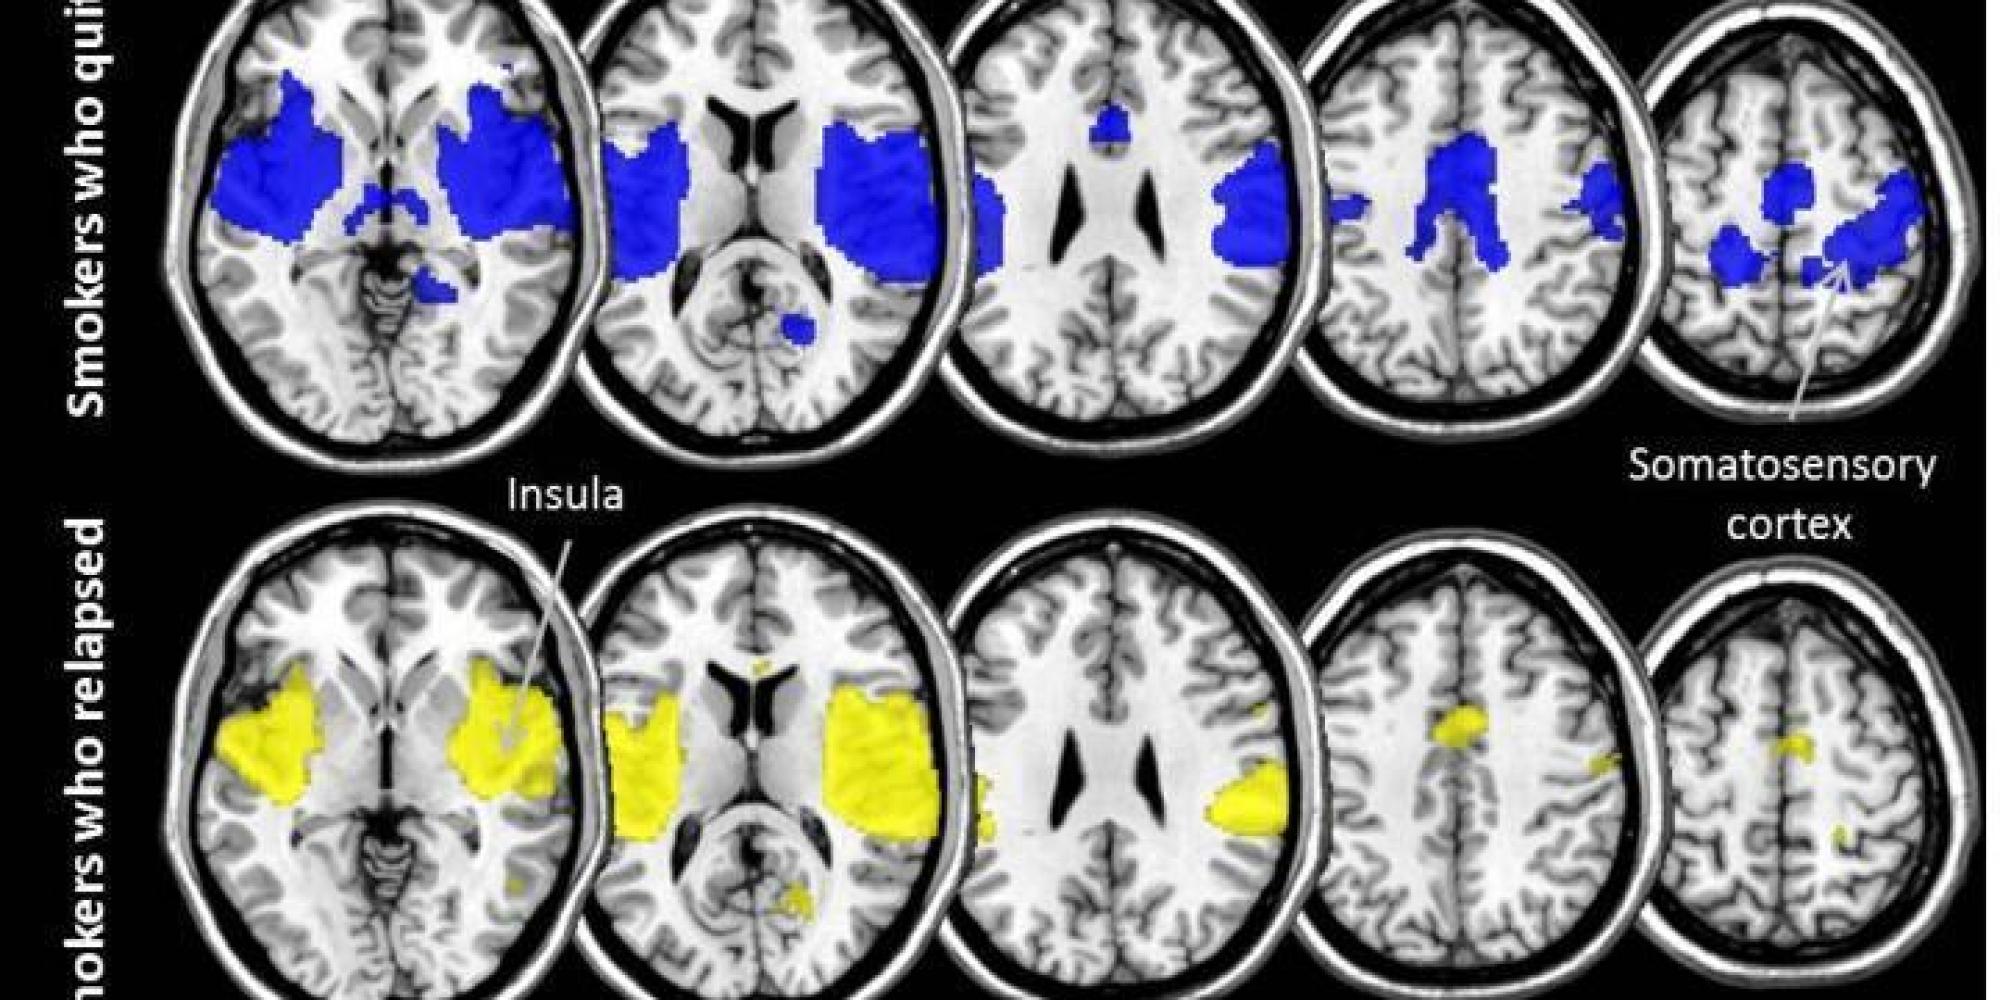

From www.cnn.com

Quitting smoking relies on stronger brain networks CNN Smoking And Brain Function In most studies, exposure to smoke is associated with increased risk for negative preclinical and cognitive outcomes in younger people as well. Chronic smoking is related to global brain atrophy and to structural and biochemical abnormalities in anterior frontal regions,. Smoking reinforcement could be due to the initial cognitive improvement, that is, individuals can learn that smoking temporarily increases. Cigarette. Smoking And Brain Function.

From www.huffingtonpost.com

What Studying The Brains Of Smokers Reveals About Quitting Successfully Smoking And Brain Function Smoking reinforcement could be due to the initial cognitive improvement, that is, individuals can learn that smoking temporarily increases. Chronic smoking is related to global brain atrophy and to structural and biochemical abnormalities in anterior frontal regions,. In most studies, exposure to smoke is associated with increased risk for negative preclinical and cognitive outcomes in younger people as well. Cigarette. Smoking And Brain Function.